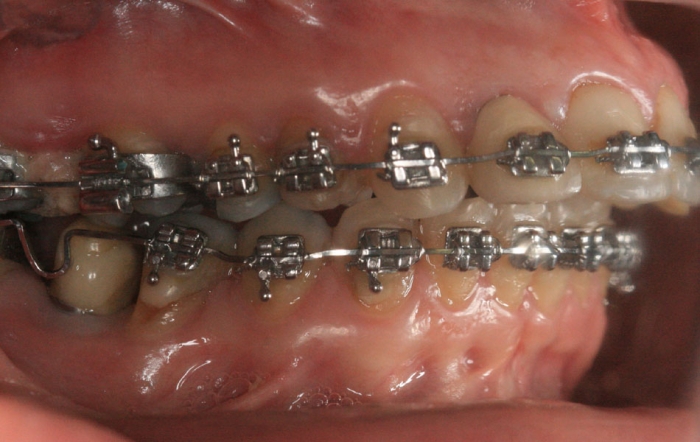

Mordida inicial

Mordida final